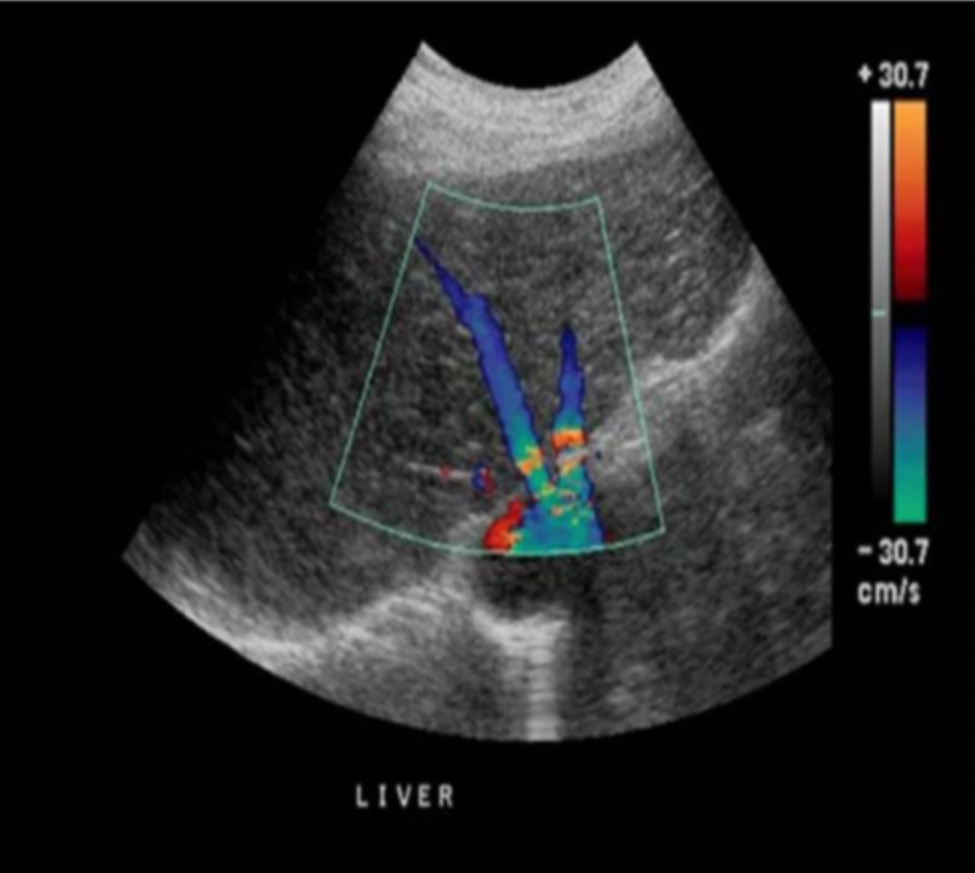

Which of the following describes the best way to eliminate the color Doppler aliasing in the proximal hepatic veins while maintaining proper flow display in the distal hepatic veins?

a. increase the color velocity scale to 0.60m/s

b. increase the color velocity scale to 0.40m/s

c. invert the door baseline

d. decrease the color priority

increase the color velocity scale to 0.40m/s

Which of the following correctly describes the color displayed on the image?

a. the color scale should be reduce so that the entire vessel is filled with red color

b. the heel-to-toe method can be used to change the course of the vessel across the image and this will allow the vessel to accurately display a single color

c. the color scale should be reduced so that the entire vessel is filled with blue color

d. the red and blue color indicate that flow is moving in two different directions simultaneously in the vessel

the heel-to-toe method can be used to change the course of the vessel across the image and this will allow the vessel to accurately display a single color